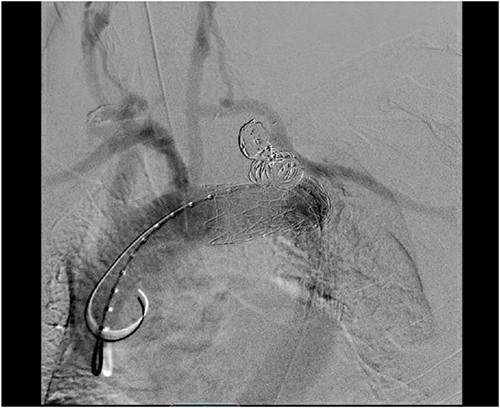

The patient’s post-operative course was uneventful, and he was discharged home on post-operative day 6 from the initial operation and on post-operative day 3 from TEVAR. CT angiography done prior to discharge revealed successful exclusion of the left SAA without endoleak and a patent left common carotid to left subclavian bypass and transposed left vertebral artery (Fig. 5). The patient had repeat imaging 3 months post-procedure that again redemonstrated the above findings.

CT angiogram showing patency of the left carotid to subclavian artery bypass graft with vertebral artery implantation and showing coil embolization of the proximal left SAA.